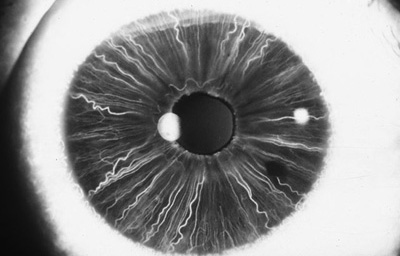

En la cara Posterior se ven pliegues radiales muy finos que se extienden desde el margen pupilar hasta el collarete ( miden ± 1.0 mm), y son conocidos como Pliegues radiales de contracción de Schwalbe. Existen ademas los llamados Pliegues estructurales de Schwalbe que son mas gruesos y mas distanciados en la porción ciliar de la cara posterior

Cara posterior de Iris: incluye Iris y Cuerpo Ciliar, Foto tomada de globo ocular de banco de ojos.